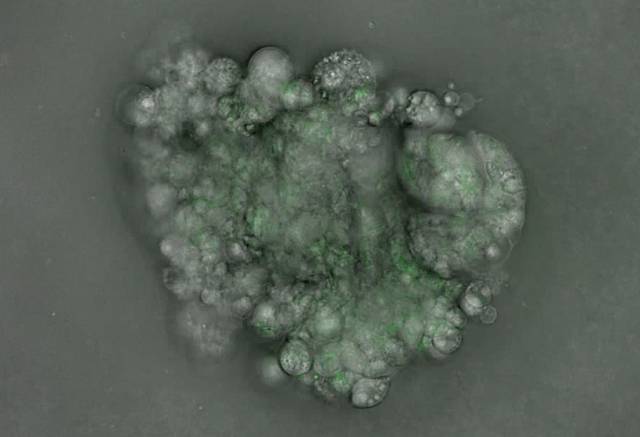

국내 연구진이 다양한 박쥐 유래 바이러스를 분석하고 치료제 반응까지 실험 가능한 세계 최대 규모의 오가노이드(사진·유사장기) 실험 플랫폼을 구축했다.

과학기술정보통신부는 14일 기초과학연구원(IBS) 공동 연구팀이 한국에 서식하는 박쥐로부터 장기 오가노이드를 만드는 데 성공했다고 밝혔다. 이 연구 결과는 세계 최고 권위의 학술지 사이언스에 게재됐다.

박쥐는 신종 코로나바이러스 감염증(코로나19), 메르스 등 고위험 인수공통 바이러스의 자연 숙주다. 하지만 지금까지 박쥐 바이러스 연구에 쓰이는 생체모델은 일부 종의 단일 장기에 국한돼 다양한 종류의 바이러스에 선제적으로 대응하는 데 한계가 있었다. IBS 연구진은 한국과 동북아, 유럽에 서식하는 박쥐 5종을 선정하고 기도·폐·신장·소장 등 장기를 본뜬 세계 최대 규모의 오가노이드를 제작했다. 오가노이드 분석 결과 연구진은 동일한 바이러스여도 종이나 감염된 장기에 따라 민감도가 다르다는 사실을 발견했다. 향후 인간에게 올 가능성이 큰 바이러스가 어떤 박쥐에서 유래할 것인지 예측할 수 있게된 것이다.